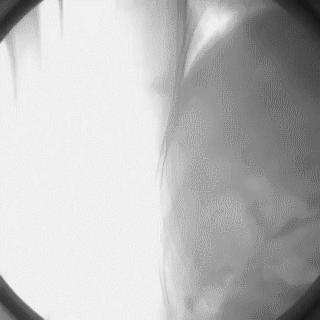

2014年,Patel T等首先采用球囊辅助通过技术(Balloon-assisted tracking,BAT),用于通过桡动脉途径中扭曲、细小节段(包括严重痉挛节段)(图1-2)。

图1

图2 BAT技术应用实例1。52岁女性患者冠脉严重痉挛(A),注射2次鸡尾酒后仍未缓解(B),采用BAT技术(C),顺利介导7F指引导管通过桡动脉严重痉挛节段(D)